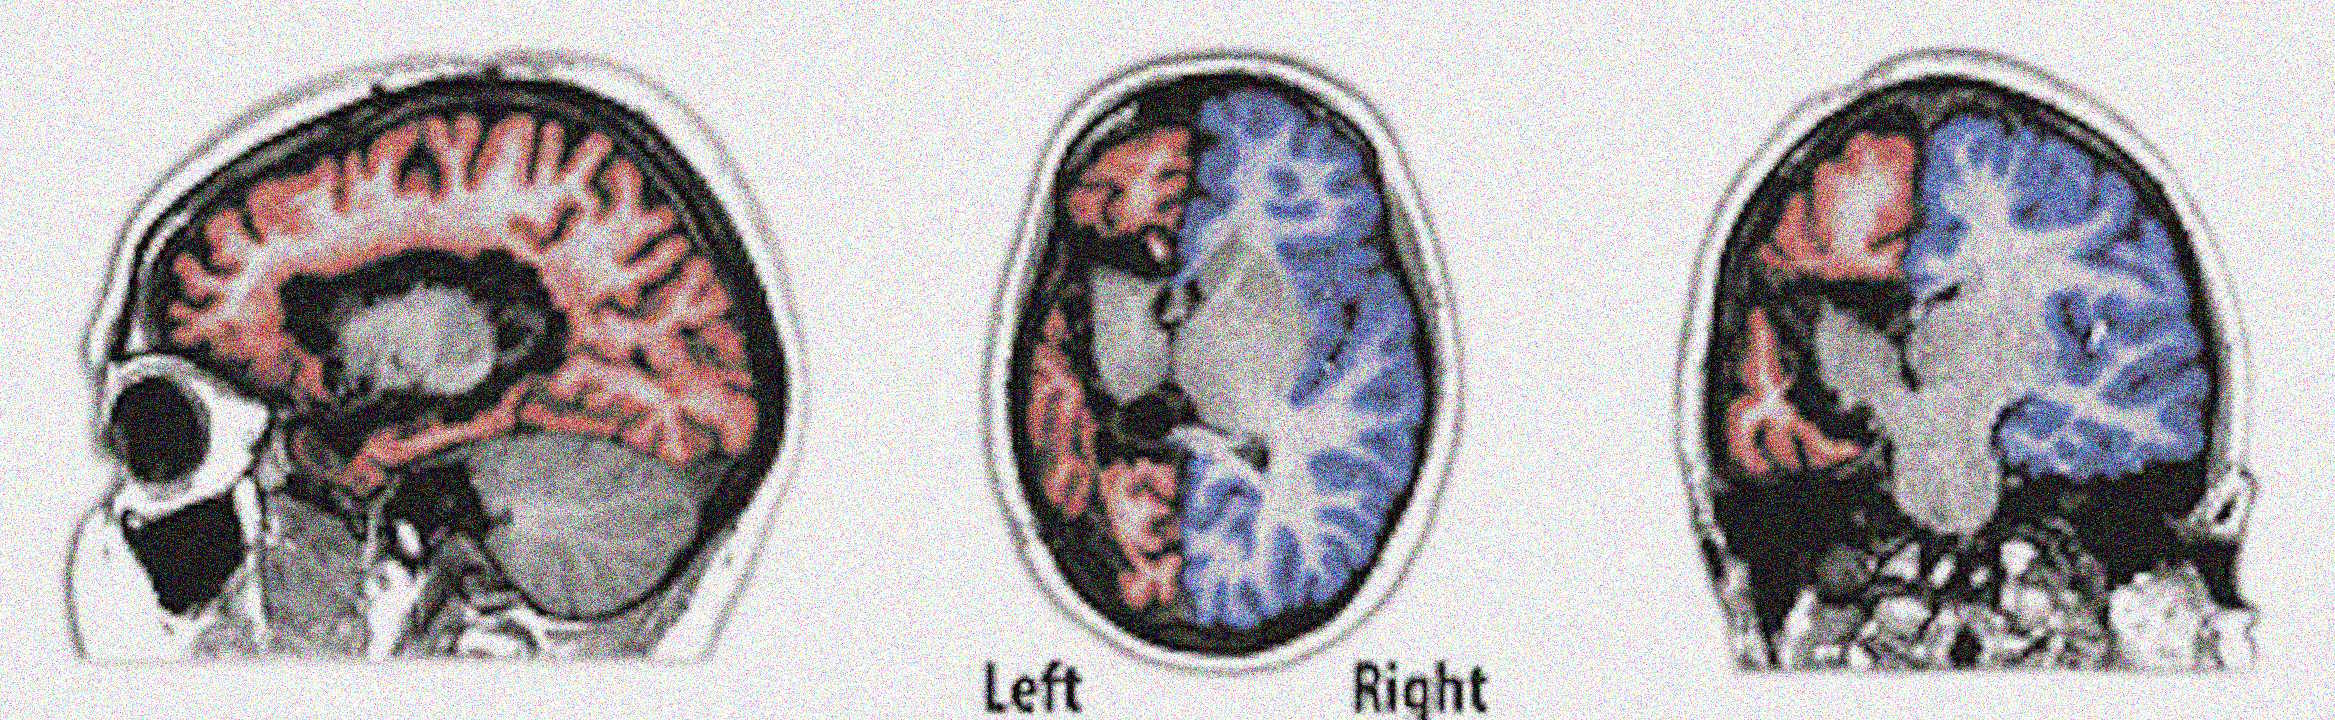

Ділянки мозку пацієнтів із епілепсією, ізольовані від решти мозку (позначені червоним). Colombo et al. / PLOS Biology, 2025